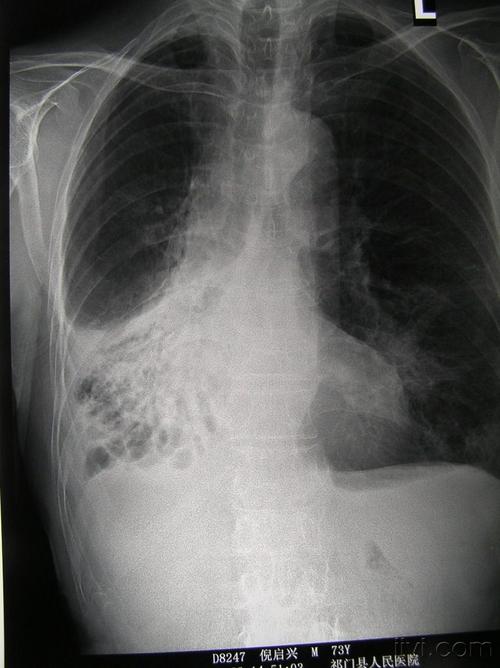

肺部有阴影,肺部有阴影是什么原因

又一个病例讨论-咳嗽,黄痰,肺部阴影

左下肺阴影,求指导

肺部出现阴影可能预示多种疾病

肺部有阴影是什么原因

肺部阴影诊断

肺部阴影图片

肺部阴影图片胸片

肺部阴影x光片